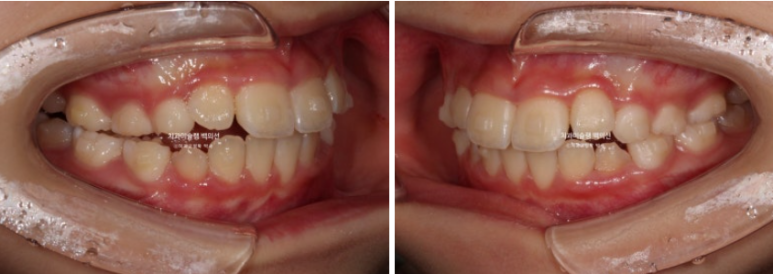

23.06~25.06

남아있는 유치는 없고 완전한 영구치열에 접어들었습니다.

나중에 2차교정을 안해도 될 정도가 되었습니다.

총 치료기간은 2년이고 중간에 쉬는 기간은 5개월이었습니다.